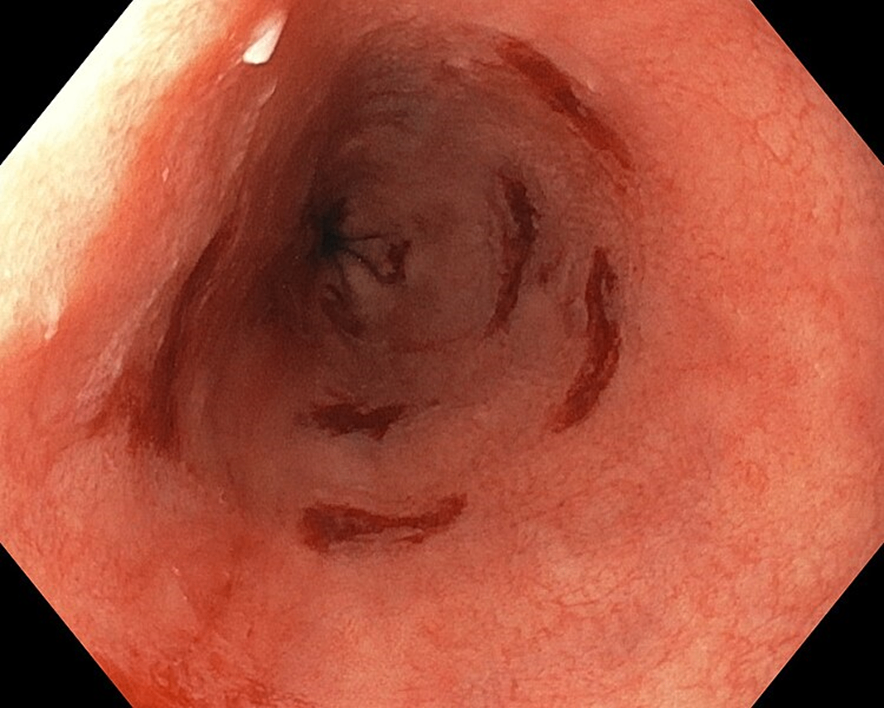

60세 남자가 6개월 전부터 발생한 속쓰림과 삼킴곤란으로 병원에 왔다. 상부내시경 검사에서 위식도이음부로부터 2 cm 떨어진 하부식도에 반점 모양의 선홍색 변화가 있다. 조직검사 소견이다. 추적관찰해야 하는 합병증은?

• 해당 환자에서는 지속된 위식도 역류로 인한 Barrett’s esophagus가 관찰된다. Barrett’s esophagus는 지속된 위식도 역류로 인해 esophagogastric junction에서 편평상피세포가 원주상피세포로 화생하며 생긴다.

• 증상으로는 속쓰림, 연하곤란 등이 나타난다. 밑의 사진에서 식도 점막의 빨간 부분이 화생이 일어난 부위이다.